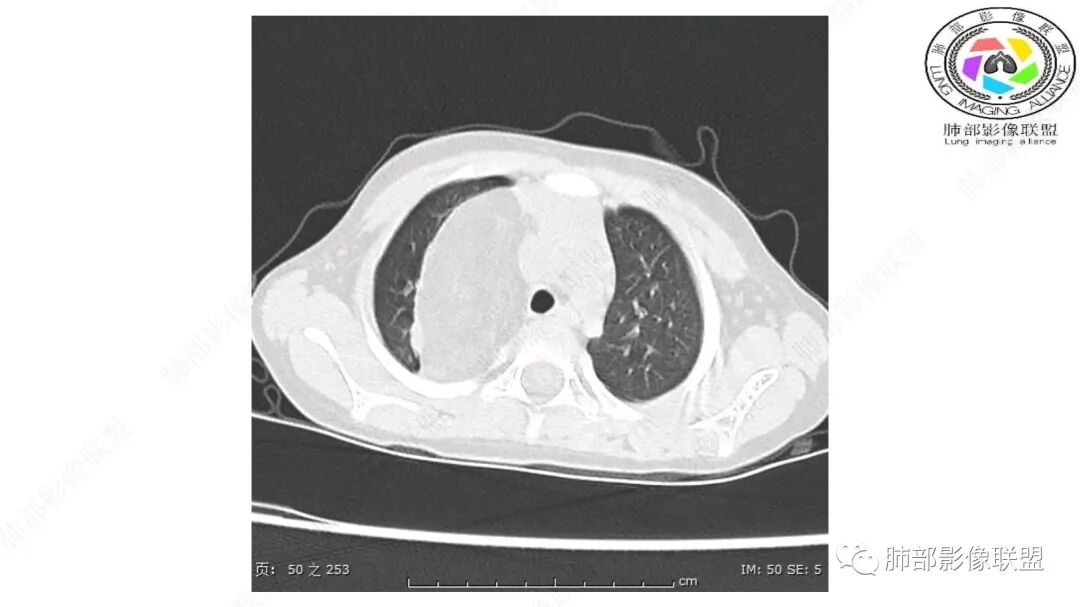

第一个问题:定位:肺内?纵隔?

病灶属于交界区,主体位于肺内,占位效应明显,前方突入胸壁,胸腺受压变形,胸膜显示欠清楚;病灶包绕上叶肺动脉;似乎有体动脉供血。符合肺内的点:包绕上叶肺动脉分支;符合纵隔的点:前方似乎突入胸壁,与胸腺关系比较密切,但是与上腔静脉的关系提示病灶不支持纵隔来源,前纵隔的常规会将上腔静脉受压后移、外移,这是不符合的。

从这个角度符合肺内的,有一点不太踏实的是:似乎突入前胸壁。

手术记录:见右肺上叶肿物,肿物与右肺上叶关系密切。与纵隔无粘连,逐步分离肿物,见肿物大小约6cm*5cm,边界清楚,于右肺上叶粘连,边界清楚,肿物包绕右肺上叶血管及支气管。超声刀逐步游离肿物,完整切除肿物,右肺上叶肺组织无破溃,表面无出血。

1.右上肺-纵隔交界区巨块影,主体位于右肺一侧,紧贴胸腺、头臂干、右锁骨下动脉、上腔静脉、奇静脉等,不能分离,但病灶整体边界清楚。注意上述相邻腔静脉等结构未见受压变形,纵隔亦未见明显向左推移,至少提示两点:

1)病灶相当柔软。

2)位于纵隔内或纵隔胸膜的可能性较小,因为受纵隔胸膜反作用力影响不明显。

2.肺动脉穿行也许是肺内来源最重要支持点!